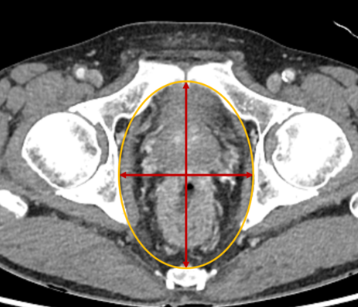

| 골반내용물적출술 | 암 치료를 위해 골반 내 장기 제거 |

골반수술은 다양한 질환과 상태를 해결하기 위해 시행됩니다. 자궁암, 난소낭종, 골반장기탈출증 등의 질환에 따라 적합한 수술 방법이 선택됩니다.